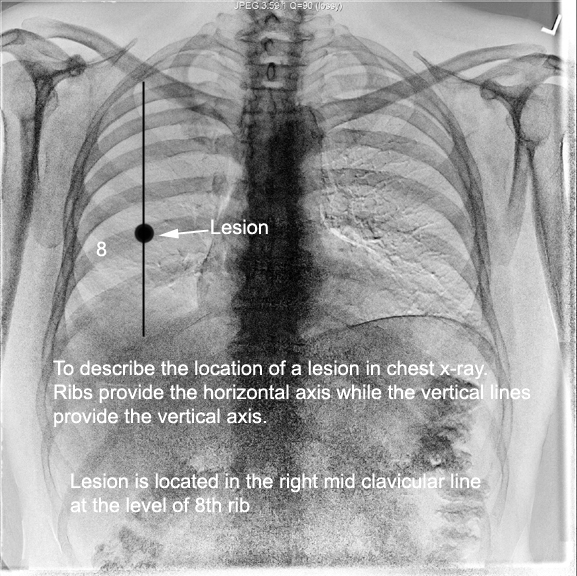

Many structures of the chest are readily visible on a chest x ray but others are difficult to see. It is the most complete reference of human anatomy available on web ipad iphone and android devices. In fact some important structures such as the phrenic nerve are not visible at all.